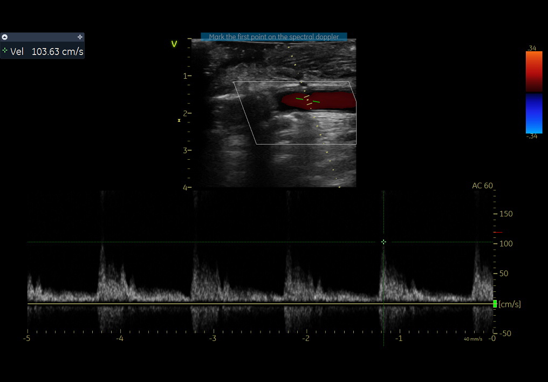

通过右肱动脉置入球囊,术中制造临时性Ⅰ型内漏,实现头臂干血流70%、左颈总动脉60%、左锁骨下动脉40%-50%的维持。